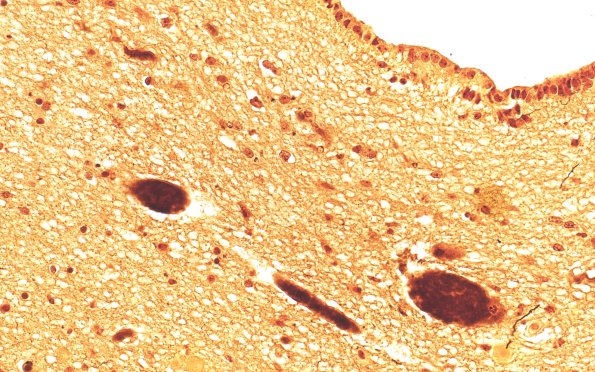

Washington University Experience | NEURODEGENERATION | Progressive Supranuclear Palsy (PSP) | 17C1 Progressive Supranuclear Palsy (PSP) (Case 17) N6 PAG Biels 40X 2

Tangles within the remaining neurons of the PAG. (Bielschowsky)